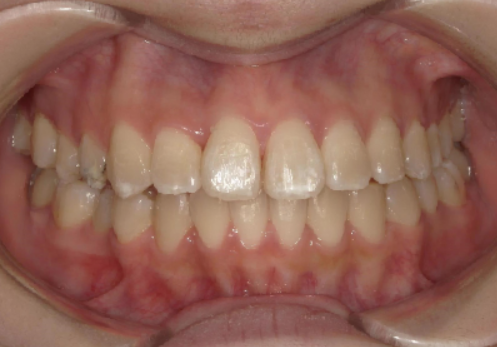

AFTER